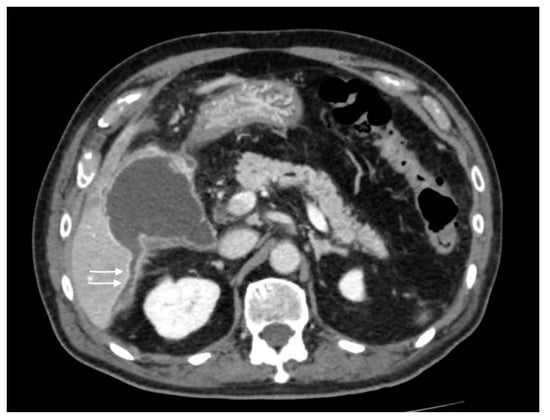

Acute portal vein thrombosis is an uncommon condition caused by the formation of a thrombus within the portal vein, as the inflammatory insult persists. Besides acute cholecystitis, it could be diagnosed as a complication of many other conditions, such as diverticulitis, urinary and pelvic infections, and malignancies [23,24]. Symptoms may be subtle, often masked by the underlying condition. CT and US are the main modalities for the acute assessment of PVT. The lack of enhancement within the vein lumen and an enlarged portal vein are the two main classic imaging CT features [24,25]. CT, unlike US, is also able to evaluate the extension of the thrombus and to detect associated findings, such as hepatic hyperemia (Figure 10), or complications, such as enteric ischemia or intra-abdominal collections [24]. Suppurative thrombosis of the portal vein, also known as pylephlebitis, is a life-threatening condition that requires early diagnosis and therapeutic assessment. The exact pathogenesis is not well known, but it is proven that specific bacterial species, such as Bacteroides Fragilis, play a key role in favoring a protrombothic state [26] and the clinical features of sepsis. As regards PVT, CT evaluation is meaningfully superior to ultrasonography for the diagnosis. Consequent to hepatic artery overflow due to PVT occlusion, transient contrast enhancement of the adjacent hepatic parenchyma during the arterial phase may occur, as well as hepatic microabscesses (Figure 11) [27]. Although not seen in most cases, CT may detect the presence of air within the thrombus as a hypodense focus within the thrombosed PV [24].

Figure 10.

Right portal vein thrombosis: extensive right portal vein hypodensity subsequent to an intraluminal thrombus formation (black arrows) with hepatic hyperemia (white arrows).